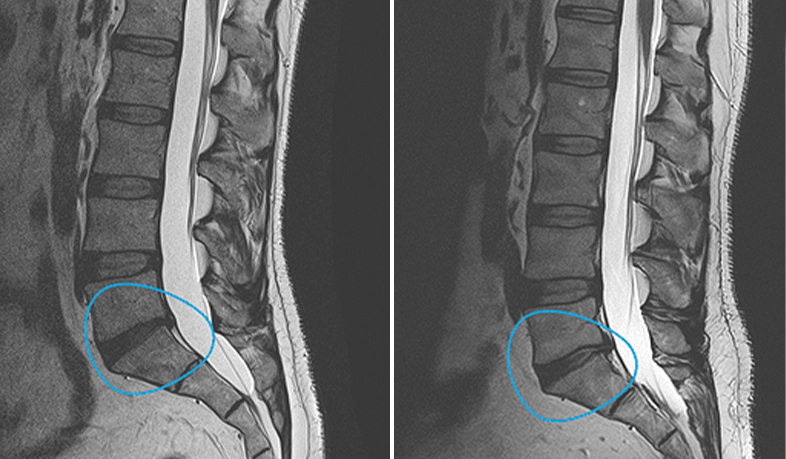

Treatment of various pathologiesWe can treat conditions like osteoarthritis (knee, hip, elbow), tendon tears and injuries (Achilles, patellar, supraspinatus), lumbar degenerative disc disease, pseudoarthrosis, osteonecrosis, xerostomia (dry mouth), and more.More info

Culture-Based Mesenchymal Stem Cell TherapyA paradigm shift in the approach to injuries, avoiding surgical operations and prostheses, and curing pathologies that were previously untreatable. It enables patients to recover quickly and effectively.